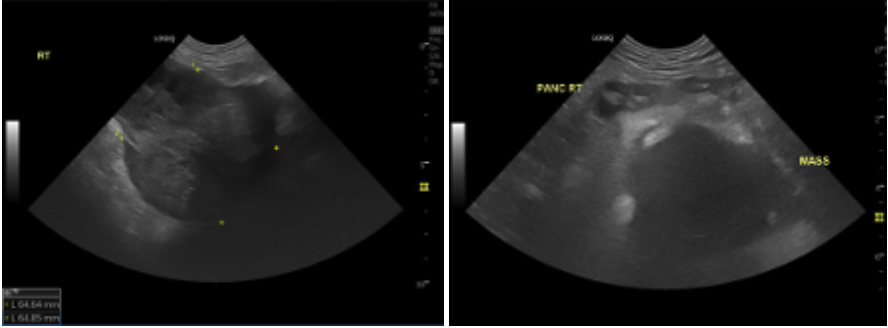

혈액검사에서는 간 수치 상승이 관찰되었습니다. 이 수치만으로 종양을 단정할 수는 없지만, 간에 부담이 가해지고 있다는 신호로 해석할 수 있습니다. 이어 진행한 복부 초음파 검사에서 우측 상복부, 간에서 유래된 것으로 보이는 큰 종괴가 확인되었습니다.

강아지 간종양 복부 초음파 검사 / 출처: 에스동물메디컬센터

해당 종괴는 내부에 낭종성 구조와 괴사가 의심되는 부위가 혼재되어 있었고, 단순 염증성 병변보다는 종양 가능성이 높은 형태로판단되었습니다. 보다 정확한 평가와 수술 가능성 판단을 위해 CT 검사를 진행하게 되었습니다.